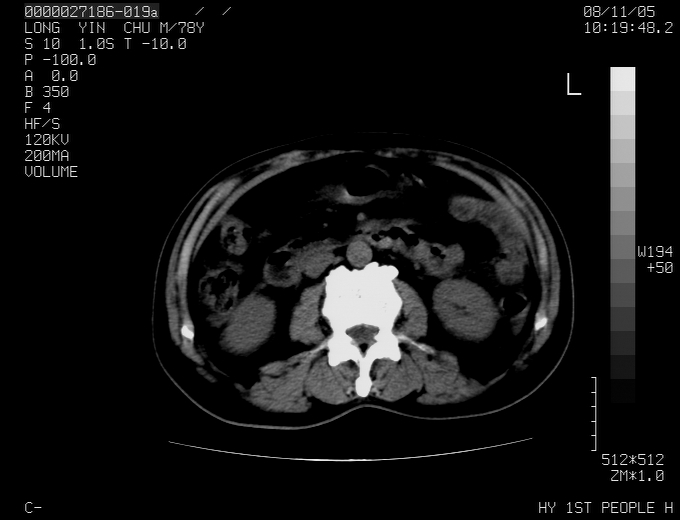

标题: CT16532:M78Y,肝脏病变,请会诊 [打印本页]

标题: CT16532:M78Y,肝脏病变,请会诊

腹胀,腹痛就诊,男性,78岁,外院b超未见异常。

肝ca,脾肾转移

支持脾肾转移瘤,双侧胸腔积液。

考虑弥漫性肝癌并脾及双肾转移.双侧胸水.

图片质量欠佳:多考虑:左侧肾癌。脾脏转移!胸膜转移!

肝脾肾转移瘤可能性大,左肾不除外梗塞,双侧胸水

考虑弥漫性肝癌并脾及双肾转移,双侧胸水。

考虑肝癌并双肾及脾脏转移;双侧胸腔积液。